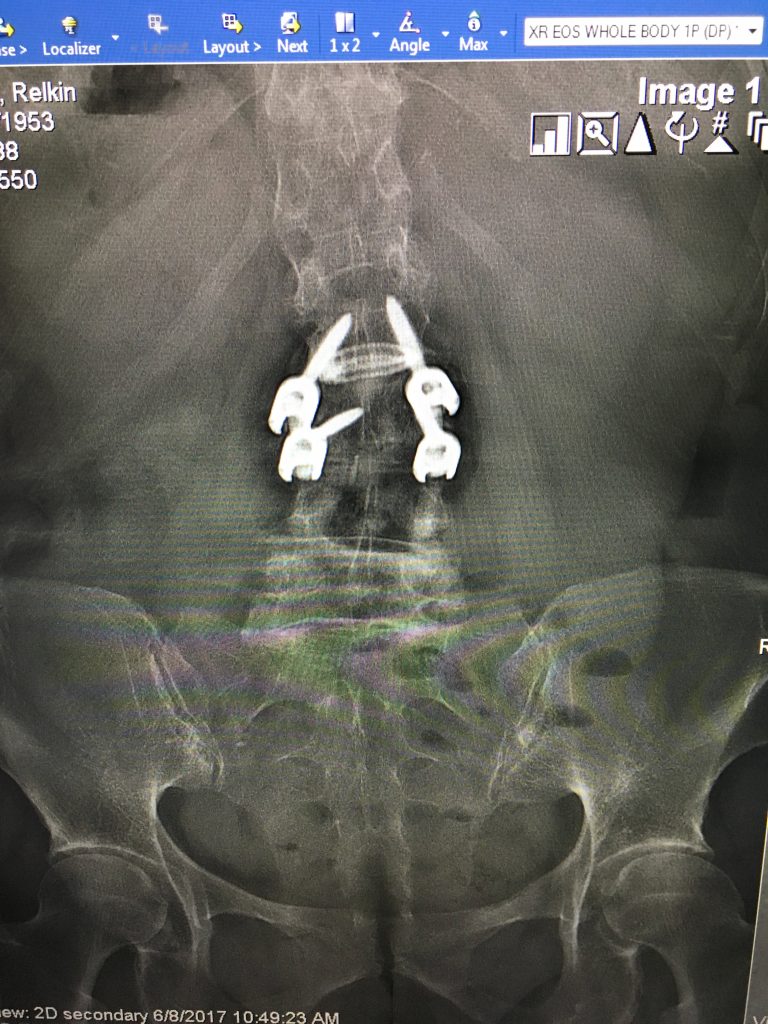

After one year of alternative therapies, including cortisone shots, nerve ablations, physical therapy, etc. to relieve referred pain that I had in my left leg, I was referred to Dr. Schwab. My pain management doctor's "bag of tricks" was in fact empty and I was advised to go forward with surgery. My husband and I interviewed 2 surgeons before we got to Dr. Schwab. At that point, I was scared and not feeling too encouraged. Meeting Dr. Schwab was like seeing a light at the end of a very dark tunnel! His calm and logical analysis totally allayed my fears and made me hopeful that I would actually be free of pain. He explained that he needed to do a fusion, opening my discs and relieving the pressure on the nerve which was clearly crushed. He also explained very clearly what I could and could not do post surgery in order to ensure its success. My surgery was a complete success- I woke up without pain and was walking 4 miles 6 days after my surgery. Not only is Dr. Schwab an incredibly gifted surgeon, he inspires complete confidence. His staff is always available via e mail or phone and the hospital experience was fabulous. I hope I will not need any other "alterations" in the future but if I do, I know who will take care of me!